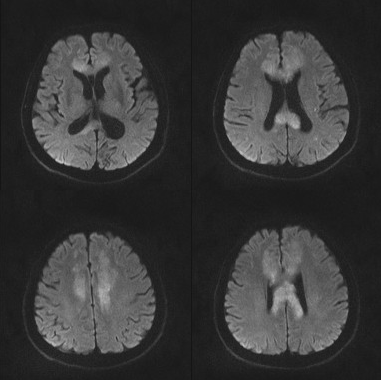

影像资料:

•急性期表现为胼胝体弥漫性肿胀,T1WI呈稍低信号,T2WI及FLAIR呈稍高信号,以矢状位观察最佳,可单独累及胼胝体压部或整个胼胝体,DWI呈高信号,ADC图呈低信号,部分患者可观察到脑室周围白质或内囊受累,少见皮层受累,表现为扩散受限,不强化和强化病例均可见到。如果增强扫描可见胼胝体有不同程度强化,呈小灶状或不规则斑片状,系血脑屏障破坏所致(如本例),本例患者处于急性期。

原发性胼胝体变性急性期:T2WI矢状位(A)清晰观察到弥漫胼胝体病变,FLAIR呈高信号(B),DWI呈高信号(C),ADC图呈低信号。

31岁,男性,长期饮酒,出现急性失语、短期注意力和记忆力缺陷,胼胝体及半卵圆中心对称性异常信号,扩散受限,未见强化,经过维生素B1/6/9/12治疗后病灶吸收明显,诊断为原发性胼胝体变性急性期。

48岁,男性,长期饮酒过量20年,出现出现眩晕,胼胝体、侧脑室周围白质、内囊后肢对称性异常信号,扩散受限,诊断为原发性胼胝体变性急性期。